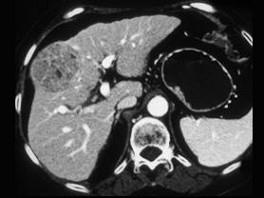

女,55岁,右上腹痛,消瘦乏力3个月,请结合图像诊断为 ( )A、肝脓肿B、肝转移癌C、肝腺瘤D、肝癌E、肝血管瘤

问题 女,55岁,右上腹痛,消瘦乏力3个月,请结合图像诊断为 ( )

选项 A、肝脓肿 B、肝转移癌 C、肝腺瘤 D、肝癌 E、肝血管瘤

答案 D